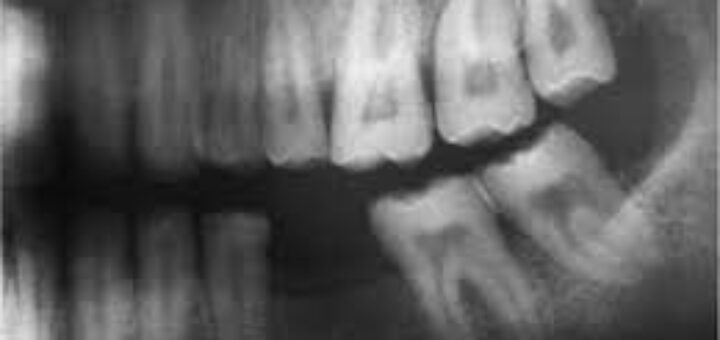

Abnormal Teeth condition: Turner Hypoplasia

Abnormal Teeth condition: Turner Hypoplasia This is an abnormality of our teeth and it isn’t that very common. A patient suffering from Turner Hypoplasia will notice abnormalities such as missing or reduced enamel on...